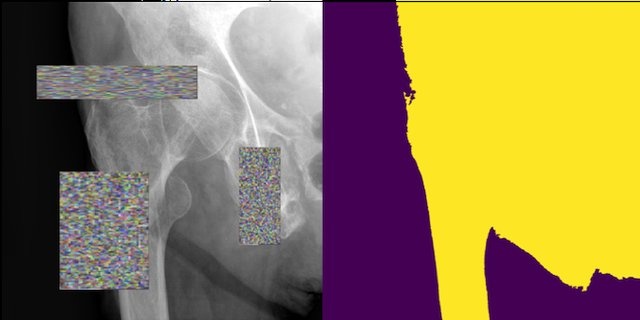

4. Transparency algorithm

The main idea of the transparency algorithm is to use the Region of Interest information to preserve the pixels at the lesion and reduce the background pixel values of the bounding box. The generated image focuses on lesion areas without losing global image context by blurring the original image except for lesion areas. The new image would still have the same distribution as the original one and a deep focus on lesions.

A new training sample (x', y') is created by transforming pixel values from the original sample (x,y) .The transformation operation can be described as:

| x' = M \odot x \newline y' = y |

The operator preserves the original label. The mask is created as follows:

| M_{ij} = \begin{cases}1 ; if (x_{min}≤i≤x_{max})\&(y_{min}≤j≤y_{max}) \\ α ; if (x_{min}>i | i>x_{max} | y_{min}>j | j>y_{max}) \end{cases} |

Where x is the image and M ∈ \{α;1\}^{W×H} is the applied mask with α as a random number that ranges from 0.0 to 0.4, and 1 is the value of pixels that is inside the lesion bounding box. Box = (x_{min},x_{max},y_{min},y_{max}) indicates the bounding box location for the abnormal image. [25]

Advantages

- Performs better than or as good as CutMix in mammograms classification [25]

- Easily applicable to any medical dataset whose images have lesions [25]